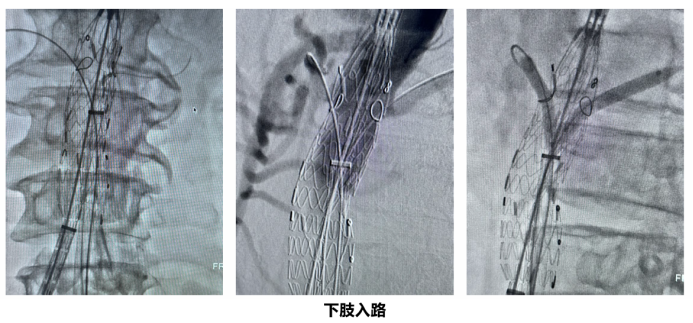

经股入路:优势与适应证

完全经股入路,即所有操作器械均通过双侧股动脉建立通路,巧妙地避开了主动脉弓区域,从根本上规避了与弓部操作相关的神经并发症风险。

经股入路的病种选择普适原则:主动脉内脏区尽量顺直,不可过于扭曲。

疾病类型:近肾腹主动脉瘤、肾上腹主动脉瘤、胸腹主动脉瘤、主动脉夹层远端动脉瘤。

其核心优势在于:

安全性提升: 脑梗风险显著降低,患者更安全。

微创性增强: 仅需股动脉穿刺或小切口,创伤小,失血量少。

普适性更广: 对主动脉弓形态的依赖性大大降低,能处理更多因弓部解剖复杂而被上肢入路拒之门外的病例。

效率优化: 术者站位更符合人体工学,透视角度更佳,有效减少辐射暴露,手术流程更流畅。